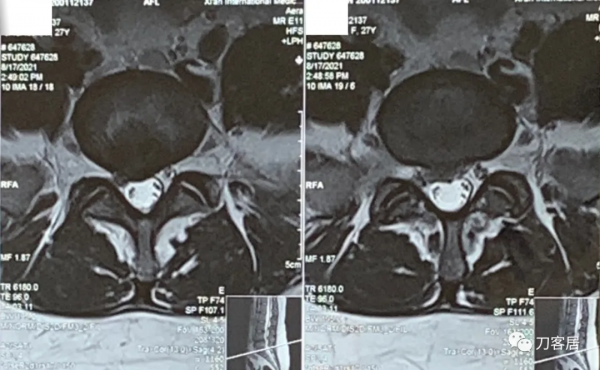

圖7. 20210817術前腰椎MRI橫截面掃描,提示L5-S1椎間盤突出,右旁中央型。